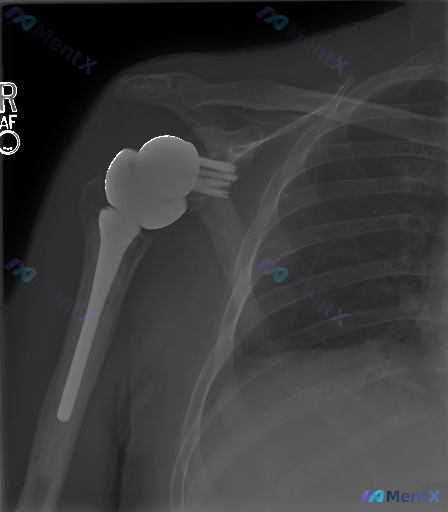

整理到一张术后随访的影像资料: - 影像类型:右侧肩关节正位X光片 - 手术史:右侧半肩关节置换术(肱骨头置换) - 初读影像印象:人工肱骨头假体形态规则,髓内柄位置居中,与肩胛盂对位尚可,未见明显的假体周围透亮线、骨折、脱位或严重骨溶解。肩部软组织也没有明显肿胀或异位钙化。 - 核心冲突:虽然初看...

整理了一份右肩关节置换术后的影像学分析资料,先把核心影像表现放出来,看看大家第一眼的读片思路会怎么走。 影像核心所见(仅基于这份单时点X光): - 可见右肩关节假体(肱骨侧柄+球头、关节盂侧底座+螺钉),位置在位 - 假体-骨界面贴合紧密,未见明显透亮线(松动征象) - 关节对位正常,无半脱位/移位...

整理了一份右肩关节正位X线片的影像资料,先给大家看常规报告的核心结论: - 右肩关节置换术后改变,假体位置良好,未见脱位/半脱位 - 肩胛盂侧固定钉位置无明显移位 - 假体周围骨质未见明确松动或骨溶解征象 - 有金属伪影,但属于正常物理表现 不过仔细看完整分析,其实藏了几个“隐性点”: 1. 金属伪...

整理到一份肩关节的影像病例,有点意思: 基础情况: - 右侧肩关节置换术后复查X光(正位) 影像科给出的显性结论: 1. 假体位置良好,无明显脱位/半脱位 2. 假体周围无明确骨折线,骨皮质连续 3. 无明显透亮带(>2mm)、骨溶解或恶性征象 4. 肩周软组织无明显钙化或广泛肿胀 但这里有个冲突点...

整理到一份右肩关节置换术后的正位X光片资料,第一眼读下来感觉很稳: - 肱骨假体位置居中,骨-假体界面没看到明显的透亮线 - 肱骨头和关节盂对位也正常,没有脱位 - 周围骨质密度还行,没看到明确骨折或破坏 - 软组织也没肿,没看到明显钙化 但资料里特别提到了几个点:金属伪影会不会挡住了什么?早期松动...